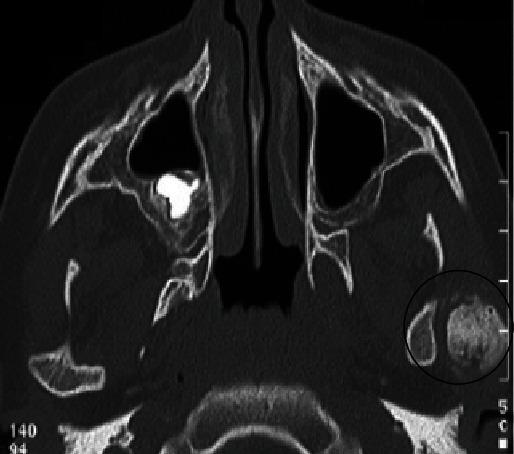

Temporomandibular joint ankylosis is an important entity that dentists and maxillofacial surgeons should know about. It clinically manifests through a permanent limitation of mandibular movements coupled with mouth opening inferior to 3 cm. This serious pathology can have serious functional repercussions, such as mastication problems, speech troubles, eating disorders, and jaw growth hindrance, in addition to the psychological difficulties in coping with such a condition in daily life. Herein, we present a radiological and chronological illustration of the evolution of temporomandibular joint ankylosis following an overlooked traumatic fracture of the mandibular condyle. The present case report involves an 8-year-old patient referred for a gradually evolving mouth opening limitation following a car accident. Tomodensitometry was helpful as it revealed an osseous block between the left temporomandibular joint surfaces, showing an ankylosis. Posttraumatic cerebral computed tomography scan was performed. It revealed an undetected fracture of the left condyle. The aim of this paper was to show how a traumatic ankylosis could have been avoided if enough attention was paid to the interpretation of immediate posttraumatic computed tomography scans. A thorough dental examination must be carried out once vital emergency is over. Early diagnosis of temporomandibular joint trauma is a crucial factor in preventing complications, such as ankylosis and its consequent oral dysfunctions. The dentist must automatically suspect condylar fracture when a child presents a history of head trauma, especially a mandibular trauma. This case should be a reminder that although temporomandibular joints are very often left out in patients' vital emergency first examination, temporomandibular joints/they are still a highly important structure which omission, and thus, dysfunction, if lesions are present, can lead to nonnegligible medico-legal consequences/that temporomandibular joints should be taken into account during patients' vital emergency first examination because if they are neglected, in the presence of lesions, they cause dysfunction, thus leading to nonnegligible medico-legal consequences.

颞下颌关节强直是牙医和颌面外科医生应该了解的一种重要病症。其临床症状表现为下颌运动永久性受限,伴张口度小于3厘米。这种严重的病理状况会产生严重的功能影响,如咀嚼问题、言语障碍、进食紊乱以及颌骨生长受阻,此外还会给日常生活中应对这种状况带来心理困扰。在此,我们展示了一例因下颌髁突创伤性骨折被忽视后颞下颌关节强直演变过程的影像学及时间顺序说明。本病例报告涉及一名8岁患者,因车祸后逐渐出现张口受限前来就诊。计算机断层扫描有助于诊断,因为它显示左侧颞下颌关节面之间存在骨块,提示关节强直。同时进行了创伤后脑计算机断层扫描,结果显示左侧髁突有一处未被发现的骨折。本文旨在表明,如果在创伤后立即进行的计算机断层扫描解读中给予足够重视,创伤性关节强直是可以避免的。一旦度过重要的紧急情况,必须进行全面的牙科检查。颞下颌关节创伤的早期诊断是预防诸如关节强直及其导致的口腔功能障碍等并发症的关键因素。当儿童有头部外伤史,尤其是下颌外伤史时,牙医必须自动怀疑有髁突骨折。这个病例应提醒人们,尽管在患者重要紧急情况的初次检查中颞下颌关节常常被遗漏,但颞下颌关节仍然是一个非常重要的结构,若存在病变而被遗漏,进而导致功能障碍,可能会引发不可忽视的医疗法律后果,即在患者重要紧急情况的初次检查中应考虑颞下颌关节,因为如果忽视它们,在存在病变时会导致功能障碍,从而引发不可忽视的医疗法律后果。